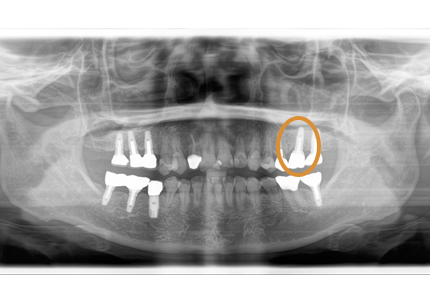

11.経過レントゲン

↑2006年4月24日

↑2008年12月

12.上顎補綴物装着(2009年5月)

24.パノラマレントゲン

↑2006年4月24日(初診時)

↑2024年6月26日

25.初診より18年経過(2024年6月26日)